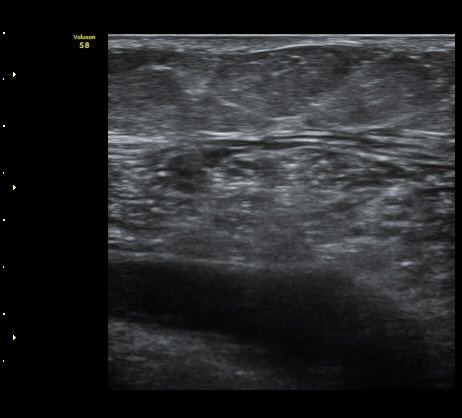

ÃÊÀ½ÆÄ À¯µµÇÏ ¼ö¾× ÈíÀÎ(÷ºÎ µ¿¿µ»ó) ÈÄ ¾Ð¹ÚºØ´ë °íÁ¤.

³»Ãø ºñº¹±Ù ÆÄ¿Àº ´ë°³ ±Þ¼ºÀ¸·Î ¹ß»ýÇÏ¿© °æÇèÀÌ ÀÖ´Â ÀÇ»ç´Â ºñº¹±ÙÆÄ¿À» ÃßÁ¤ÇÒ ¼ö ÀÖ´Ù.

±×·¯³ª °æ¹ÌÇÑ ÆÄ¿ ÈÄ ¹«¸®ÇÑ ¿îµ¿À¸·Î ÆÄ¿ÀÌ ÁøÇàµÇ´Â °æ¿ì ÅëÁõÀÌ Å©Áö ¾Ê°í º´·Âµµ ¶Ñ·ÈÇÏÁö ¾Ê¾Æ

ºñº¹±Ù ÆÄ¿À» ÃßÁ¤ÇϱⰡ ½±Áö ¾Ê´Ù. ÀÌ·± °æ¿ì¿¡´Â È®Áø¿¡ ÃÊÀ½ÆÄ°Ë»ç°¡ ÇʼöÀûÀÌ´Ù.